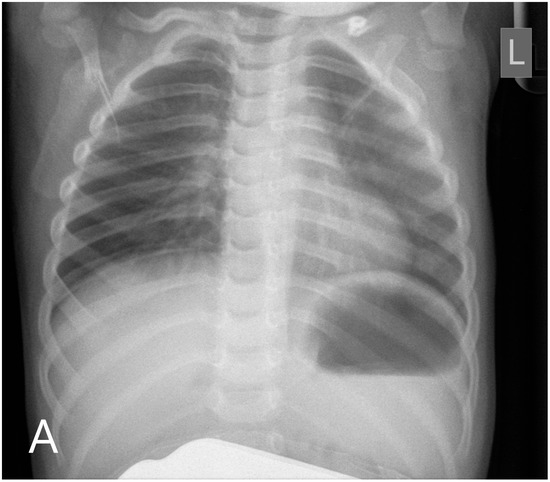

Resolution of osteopetrosis could be seen on MR imaging that took place 6 months after the transplantation, and radiography also demonstrated the recovery of the disease phenotype (Figure 2A).

Figure 2.

Chest radiography (A) shows the disappearance of skeletal malformations 6 months after the transplantation. At this time, sagittal T1-weighted MR image (B) described the unusual morphology of the calvaria: craniosynostosis.

However, radiological normalisation was not apparent in one region, the calvaria: neurocranial sutures progressed to ossify even though osteoclast resorptive function had been initiated in other parts of the skull and the skeletal system (Figure 2B). Neurosurgery was confronted with the necessity of craniotomy considering the danger of increased intracranial pressure secondary to craniosynostosis. The reconstructive operation was successfully performed. In the 15th month, at the time of the writing of the manuscript, the patient remained on an adequate course of neuromotor development, had stable haematopoiesis, and achieved recovery of the disease phenotype related to bone metabolism.